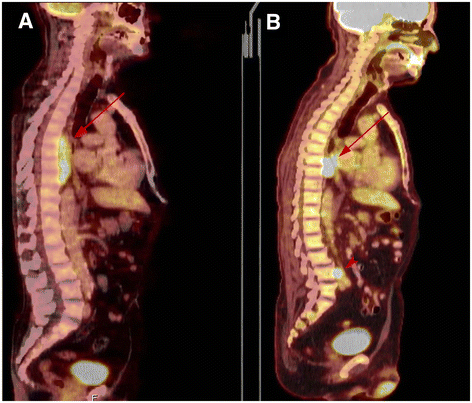

We report an unusual case of a 70-year-old male with history of hereditary spherocytosis (HS) and secondary paraspinal extramedullary hematopoiesis with a concurrent follicular lymphoma. The lesion presented as a thoracic paraspinal mass of 9 cm, extending longitudinally between T6 and T9 vertebral bodies. Incisional biopsy revealed that this mass included mature hematopoietic tissue compatible with extramedullary hematopoiesis (EMH). The tissue also presented an extensive and diffuse infiltration by an atypical lymphoid population composed predominantly by small cells. The immunohistochemical study revealed that the atypical lymphoid population had a germinal center phenotype, consistent with the diffuse variant of follicular lymphoma (FL). The simultaneous presence of both EMH and FL in the same lesion made the interpretation and the final diagnosis of this case difficult. The presence of EMH in this clinical context may eclipse the diagnosis of the underlying lymphoproliferative neoplasm. The close association between the tumor cells and extramedullary hematopoietic tissue in the absence of lymphadenopathies or other tissue involvement suggests a relationship of this tumor with the recently described primary FL of the bone marrow.